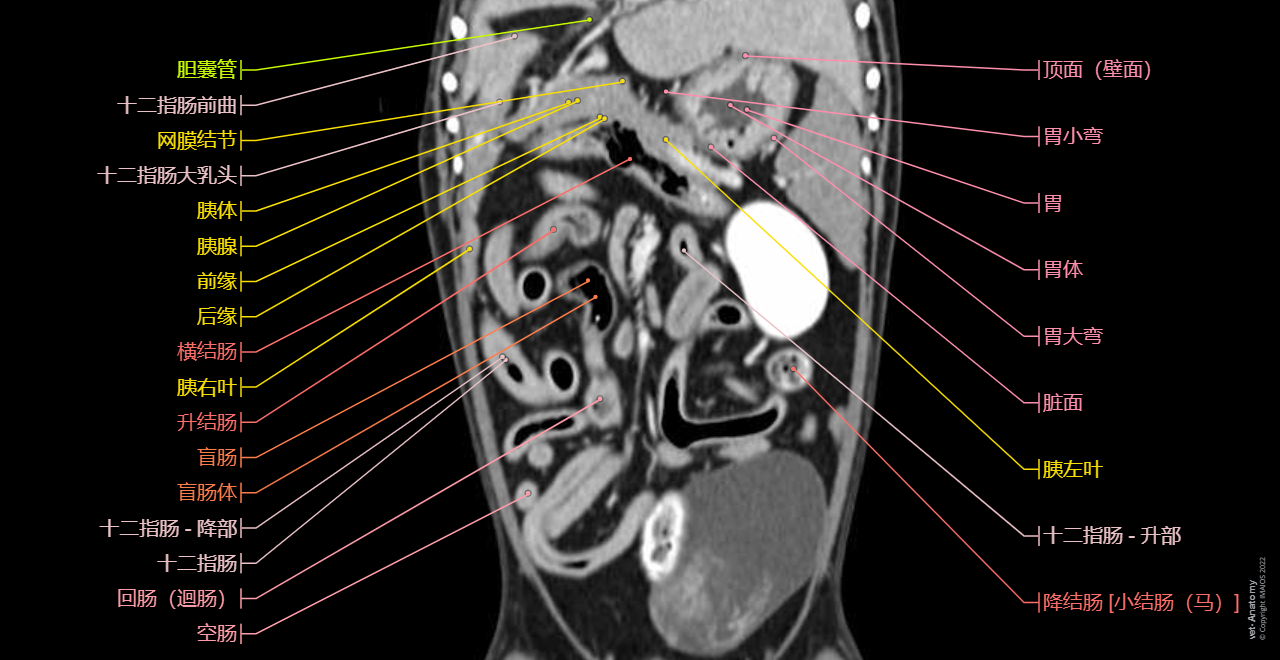

vet-Anatomy兽医图集的本模块是关于CT扫描的犬类腹部和骨盆。

CT图像来自一只健康的6岁阉割雄性犬。

在vet-Anatomy动物图集的此模块中,计算机断层扫描(CT)显示了标有解剖结构的犬科腹腔和骨盆横截面,并用3D图像显示犬科腹部。

CT图像存在3个平面方向(横向,矢状和背侧),并且使用两种对照方式(软组织/血管和骨骼)展现。本模块的末尾提供其他3D解剖图像,便于进一步了解犬科总体解剖结构,展示了骨骼、内脏(肝脏、脾脏、胰腺、消化道)、泌尿生殖系统、动脉、全身静脉系统(主要是尾腔静脉及其分支)、门静脉系统、肌肉和表面解剖的三维容积透视图。

Anatomy of the male canine abdomen and pelvis on CT imaging: Alimentar canal, Stomach, Colon

Dog - Digestive system - 3D - Anatomy: Stomach, Duodenum, Jejunum, Ileum, Small intestine, Large intestine, Colon, Rectum

Dog